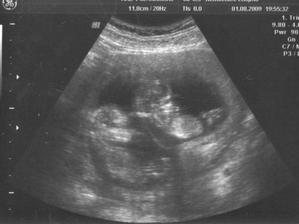

5.8.2009 jsem byla na screeningu 12tt. ve Zlíně - výsledky vyšly negativně a to i krevní. Jsem moc ráda.